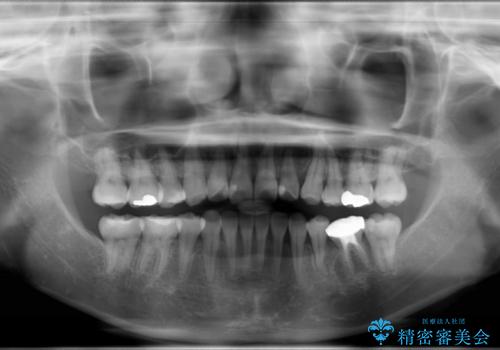

ハーフリンガル抜歯矯正 八重歯を改善する

- 30代女性

- ハーフリンガル

- 小臼歯4本抜歯によるハーフリンガル・ワイヤー矯正を計画した。

シビアな八重歯がきれいに歯列にはいることにより、笑った時の印象などもかなり大きく変わります。